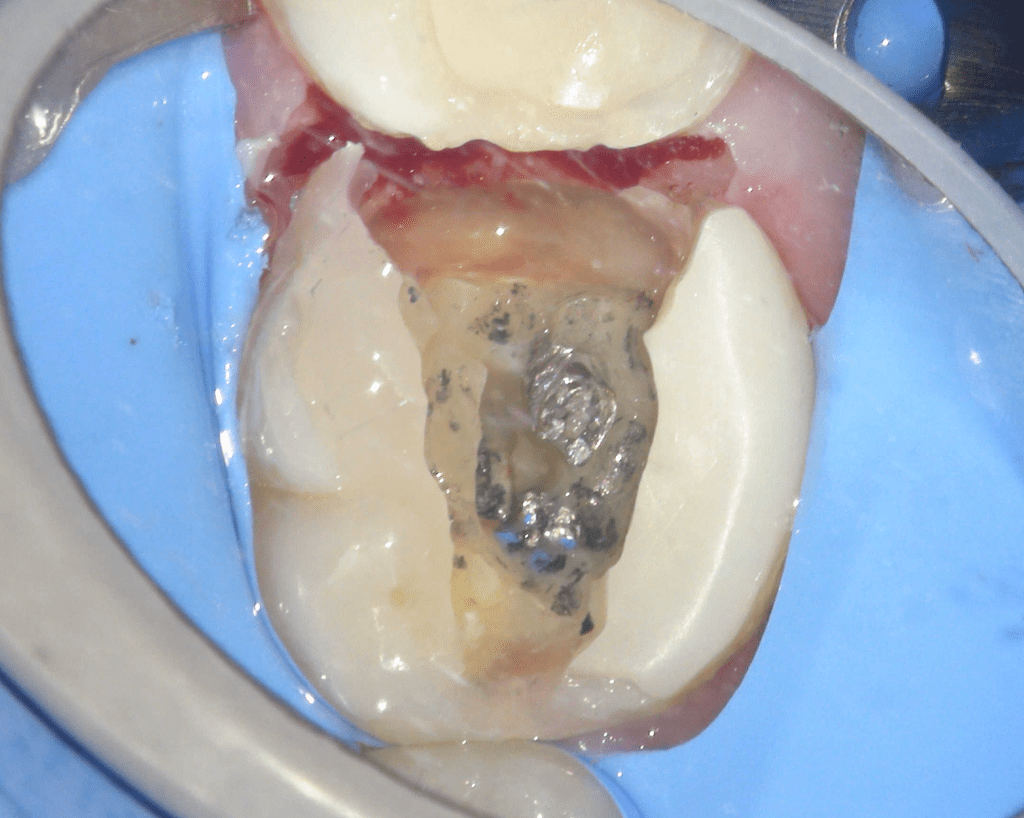

Pulpotomía biodentine + reco preendio